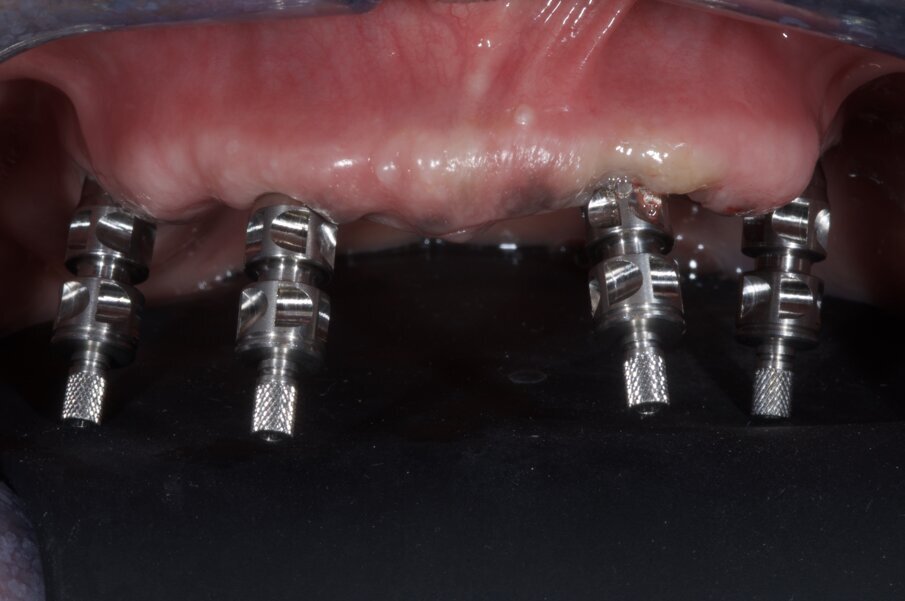

Ad impianti inseriti si procede alla connessione degli abutments MUA, all’orientamento e alla parallelizzazione dei due posteriori, ed alla presa dell’impronta in gesso (Figg. 26, 27). Dall’impronta si può verificare come la disposizione degli impianti sia perfettamente coincidente con quella pianificata con il software di chirurgia guidata. Nel caso in questione vista l’età della paziente e la sua disponibilità ad aspettare il tempo di osseointegrazione, gli impianti sono stati protetti con le cappette per i MUA e la protesi totale forata per non interferire (Fig. 28).